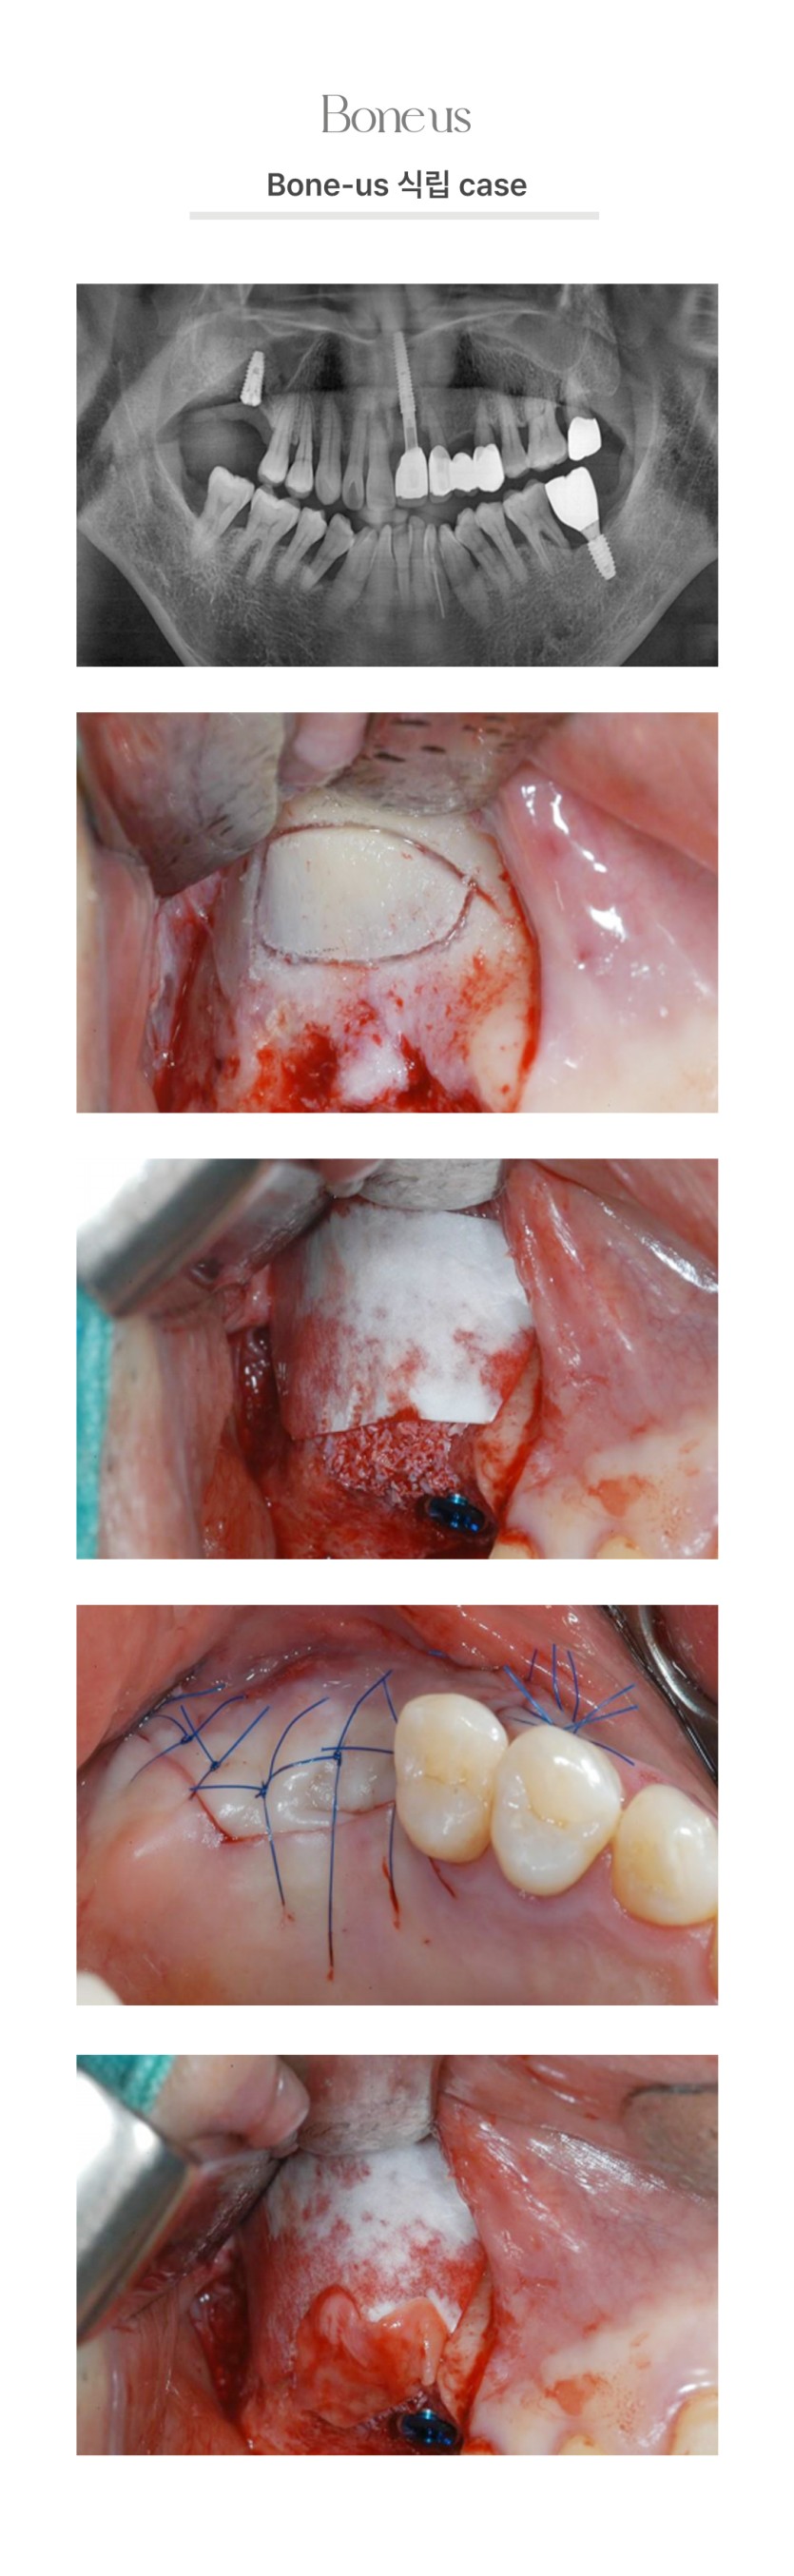

본어스 식립 케이스 9

본어스 식립 케이스 10